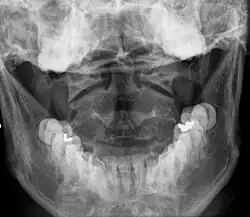

Cervical Vertebrae (C1 - C7)

Once there is an onset of the symptoms in the patient, the patients are screened through cervical-spinal imaging techniques: X-ray, CT, MRI. [1] The scanning technique points out any cervical vertebrae defects and misalignments. (Image 1. and 2.) When cervicocranial syndrome is caused as a result of a genetic disease, then family history and genetic testing aid in making an accurate diagnosis of cervicocranial syndrome.